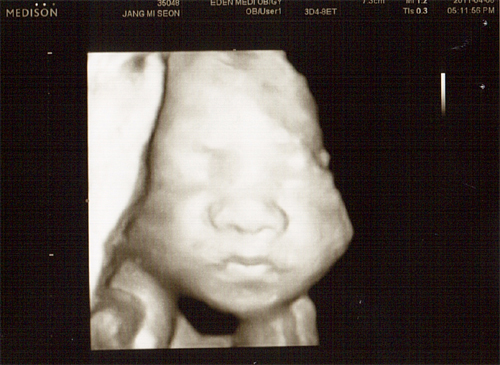

26주 4월 8일(금) 입체 초음파사진

글쓴이 : 최고관리자 날짜 : 11-04-09 09:39 조회 : 487